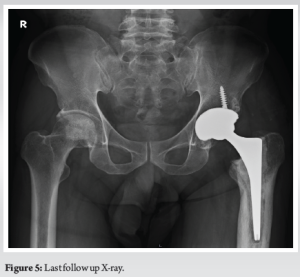

The patient, a 64-year-old male, had been leading a normal life until 15 years ago when he began experiencing left hip pain and difficulty walking. Over the following year, these issues worsened, impending his daily activities. He had a history of chronic smoking and was undergoing steroid treatment for psoriasis. Upon clinical and radiological evaluation, he was diagnosed with avascular necrosis of the left hip leading to secondary osteoarthritis. He underwent uncemented MoM THA (Corail stem with Pinnacle Cementless Acetabular cup, Metal head and Metal liner – DePuy Synthes, Warsaw, Indiana) (Fig. 1). For 15 years, he was happy with his surgery. 15 years following his index surgery, he returned with complaints of painful left hip and limping persisting for 3 months. Radiography revealed femoral stem loosening, (Fig. 2) prompting further investigation including metal artefact reduction sequences (MARS) magnetic resonance imaging (MRI) to rule out pseudotumors, which came back negative, but revealed features of synovial fluid collections around the implant site and features suggestive of aseptic loosening of the hip implant. Although his inflammatory markers were normal, his cobalt and chromium levels were 6.25 (normal range 0.01–0.91) and 5.85 mcg/L (normal range 0.70–28) indicating high cobalt levels and he underwent revision THR with the suspected cause being aseptic stem loosening due to a MoM reaction. During the procedure, we encountered dark brown synovial fluid, indicating potential metallosis, and tissue deposition around the proximal femur and intramedullary canal, which were biopsied for analysis. Biopsy report revealed pigment deposition, pigment laden macrophages and areas of necrosis consistent with metallosis (Fig. 3). The explanted Corail stem demonstrated the absence of its HA coating, which was associated with the presence of a MoM bearing (Fig. 4). He underwent a revision THR. Clinically at 1 year, he is asymptomatic and back to his day today activities(Fig 5).